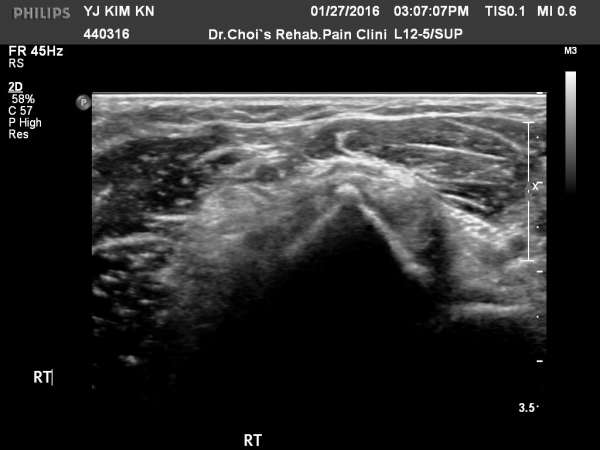

ÆÈ²ÞÄ¡ ¾Õ ÀÌµÎ¹Ú±Ù°Ç È¸´Ü¸ç°Ë»ç¿¡¼­ ÀÌµÎ¹Ú±Ù°Ç ¿ÜÃø¿¡ ¼ö¾×Àú·ù°¡ °üÂûµÊ(»çÁø 1).